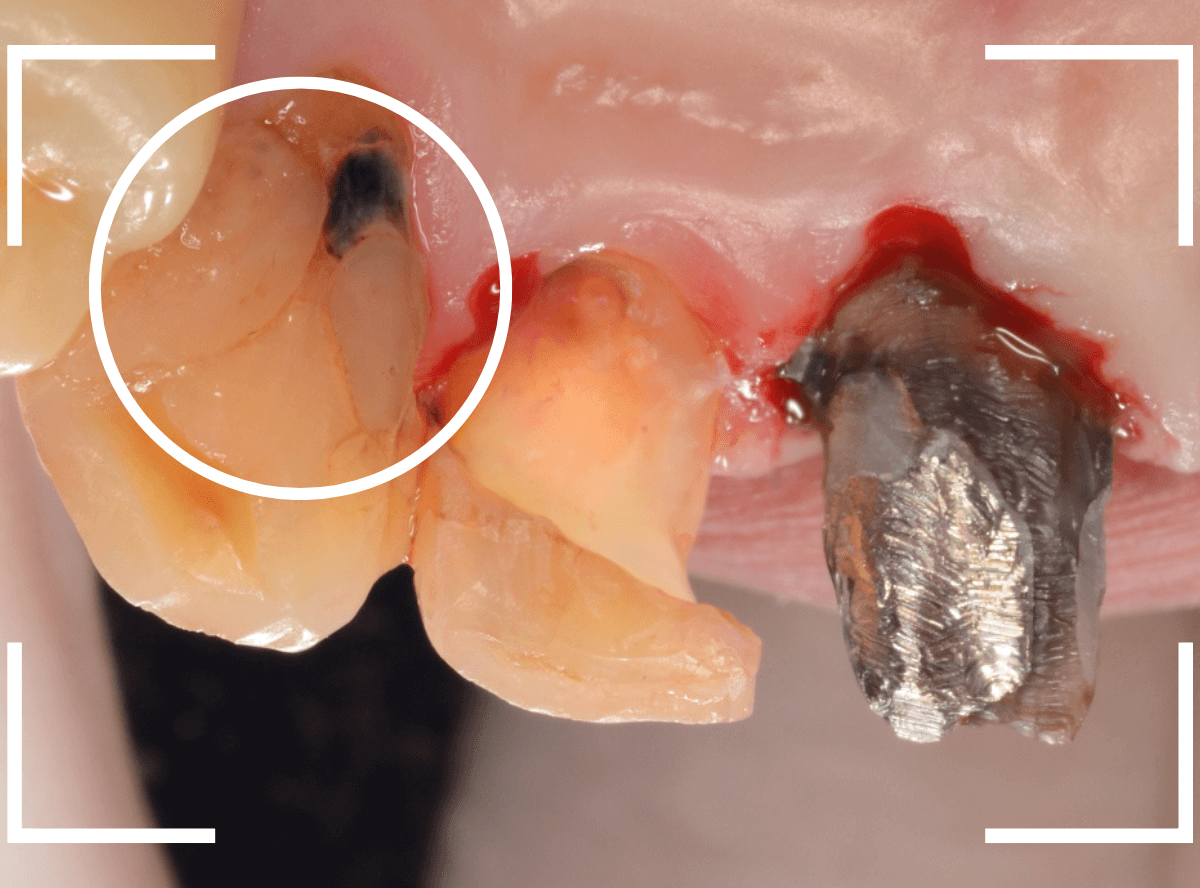

さし歯を外すと、金属の土台(メタル・コア)が出てきました。

慎重に土台を外して、中を調べます。

赤く染色されている部分が虫歯の残っているです。

慎重に虫歯を除去して、土台の型を取ります。

新たに、ファイバー・コアを製作し、setします。